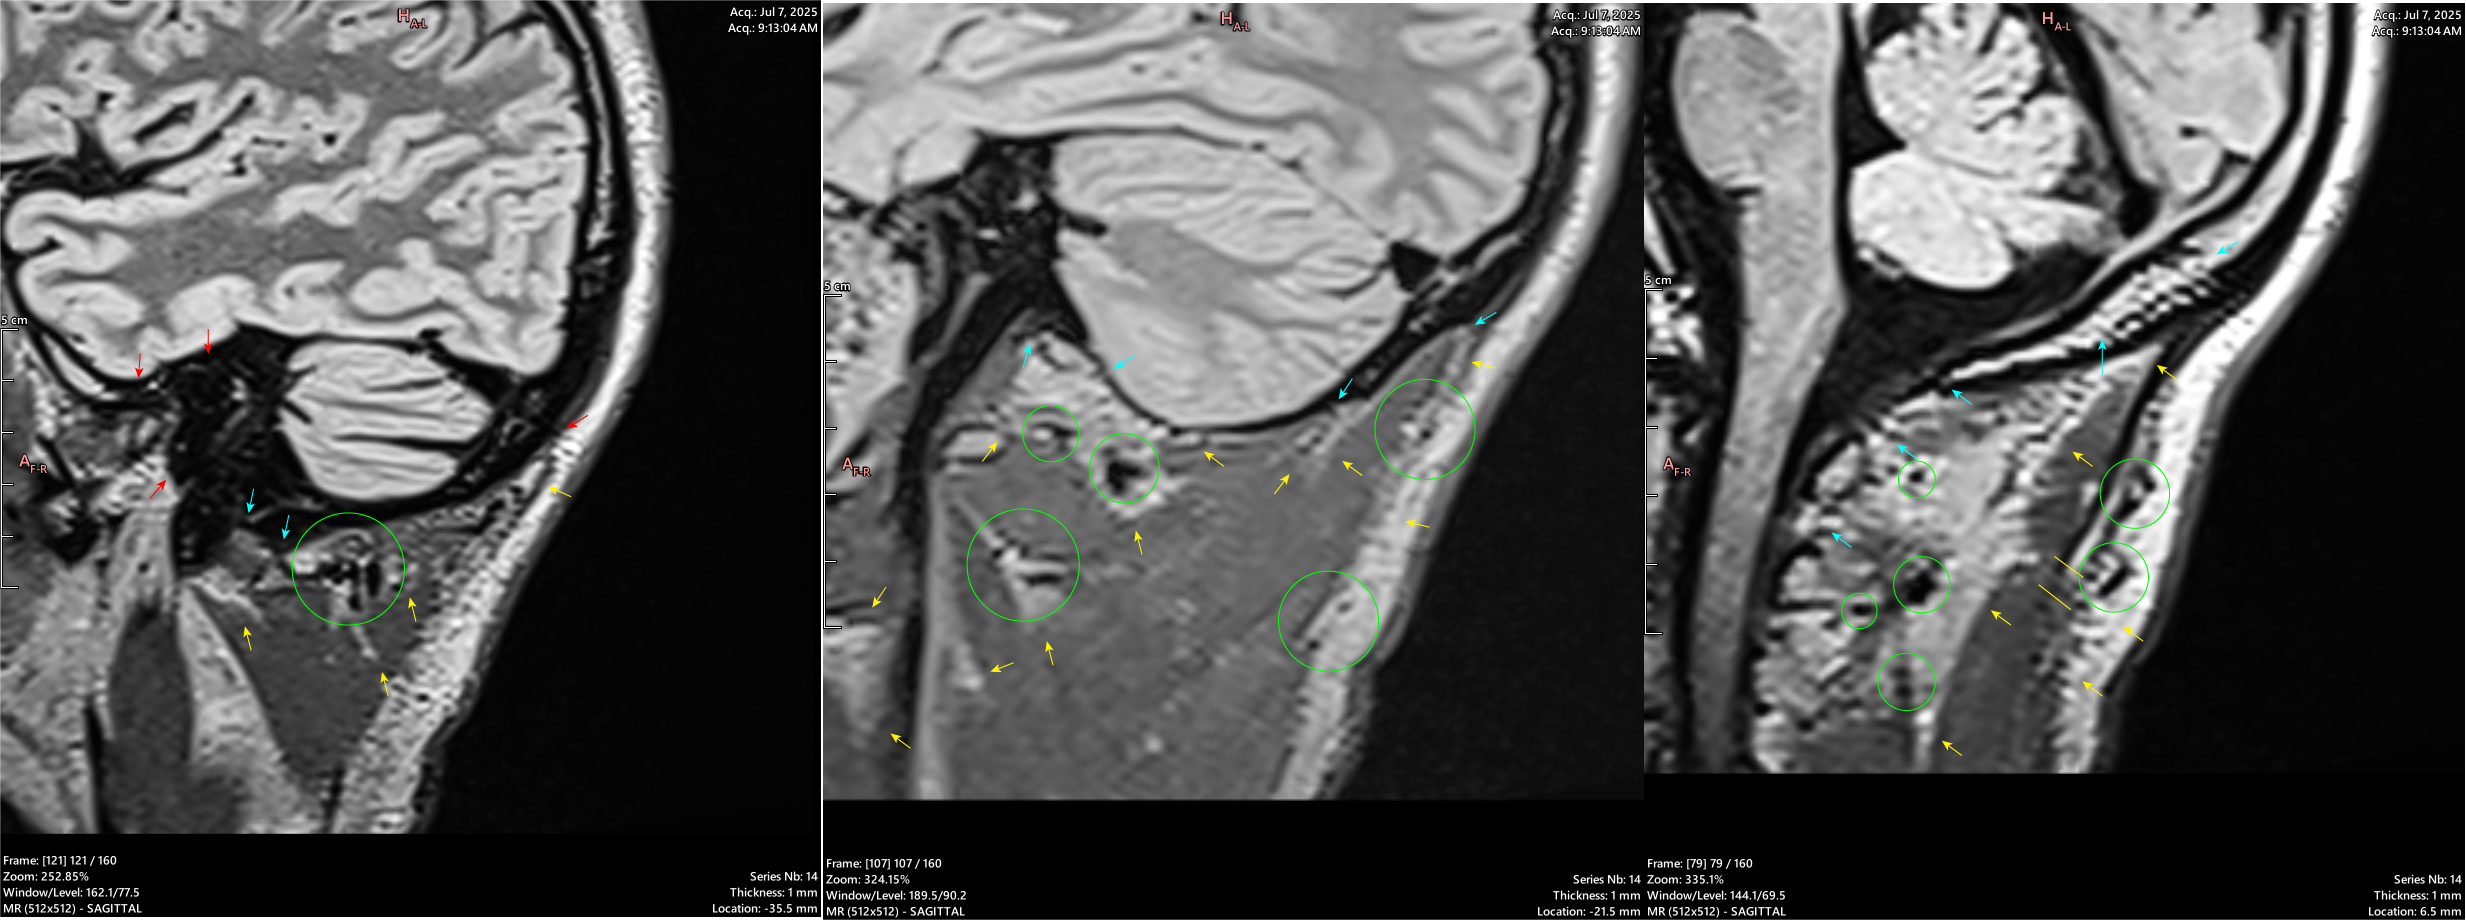

RED: Invasion of the Temporal Artery and External Carotid. Red arrow in first image at the posterior should be light blue

LIGHT BLUE: Probably CSF leak sites.

YELLOW: Subcutaneous fluid, most probably a mixture of CSF, inflammatory cells, and blood products.

GREEN: Lymph nodes.

RED: Invasion of the Temporal Artery.

DARK BLUE: Extracranial soft tissue extension.

GREEN: Main body of mass.

RED: Invasion of the Superior Sagittal Sinus.

LIGHT BLUE: Dermal Invasion.

Bone destruction and invasion of the brain parenchyma are visible locally around the SSS, as well as through the image.

RED: Invasion of the Right Inferior Cerebellar Artery. The first image shows encasement of the Artery, while the others show extension into the channel.

RED: Left of the Right Inferior Cerebellar Artery. The second image shows encasement of the Artery, while the others show extension into the channel.